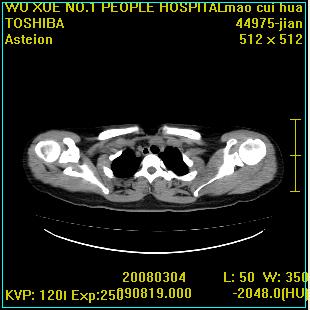

标题: CT12025:男,50岁,左肩活动受限半年。 [打印本页]

标题: CT12025:男,50岁,左肩活动受限半年。

肩关节骨质破坏呈小囊状,其周软组织轻度肿胀,余未见异常。

考虑:肩袖损伤。建议mri。

左侧肱骨头密度不均匀,高低混杂,周围软组织略肿胀,考虑结核性病变。

左侧肱骨头密度不均匀,高低混杂,髓腔密度稍高,周围软组织略肿胀,肌间隙模糊,考虑慢性骨髓炎可能。密切结合临床!

肩关节周围软组织轻度肿胀,肌间隙模糊,余未见异常。

考虑:肩周炎。